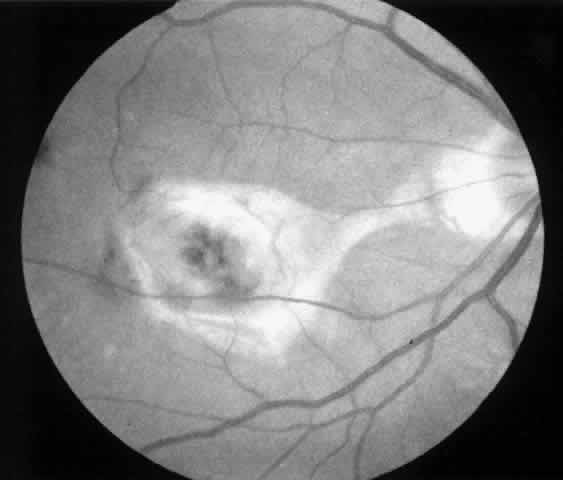

4. A 71-year-old patient with ARMD developed a recurrent choroidal neovascular membrane extending into the fovea with a preoperative vision of 20/320 (6/96) (Fig. 13). He had only marginal visual improvement after surgery (20/200 [6/60]) owing to a subfoveal RPE defect, but the size of the scotoma decreased after resolution of subretinal fluid (Fig. 14).

Fig. 13. Preoperative fluorescein angiogram (A) and Amsler grid (B) of a 71-year-old patient with age-related macular degeneration (case 4).

Fig. 14. Postoperative fundus photograph (A) and Amsler grid (B) (case 4). Central retinal pigment epithelial defect accounts for minimal visual improvement. Significant improvement is noted on Amsler grid.